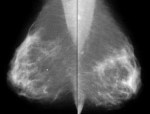

http://www.vhct.org breast cancer